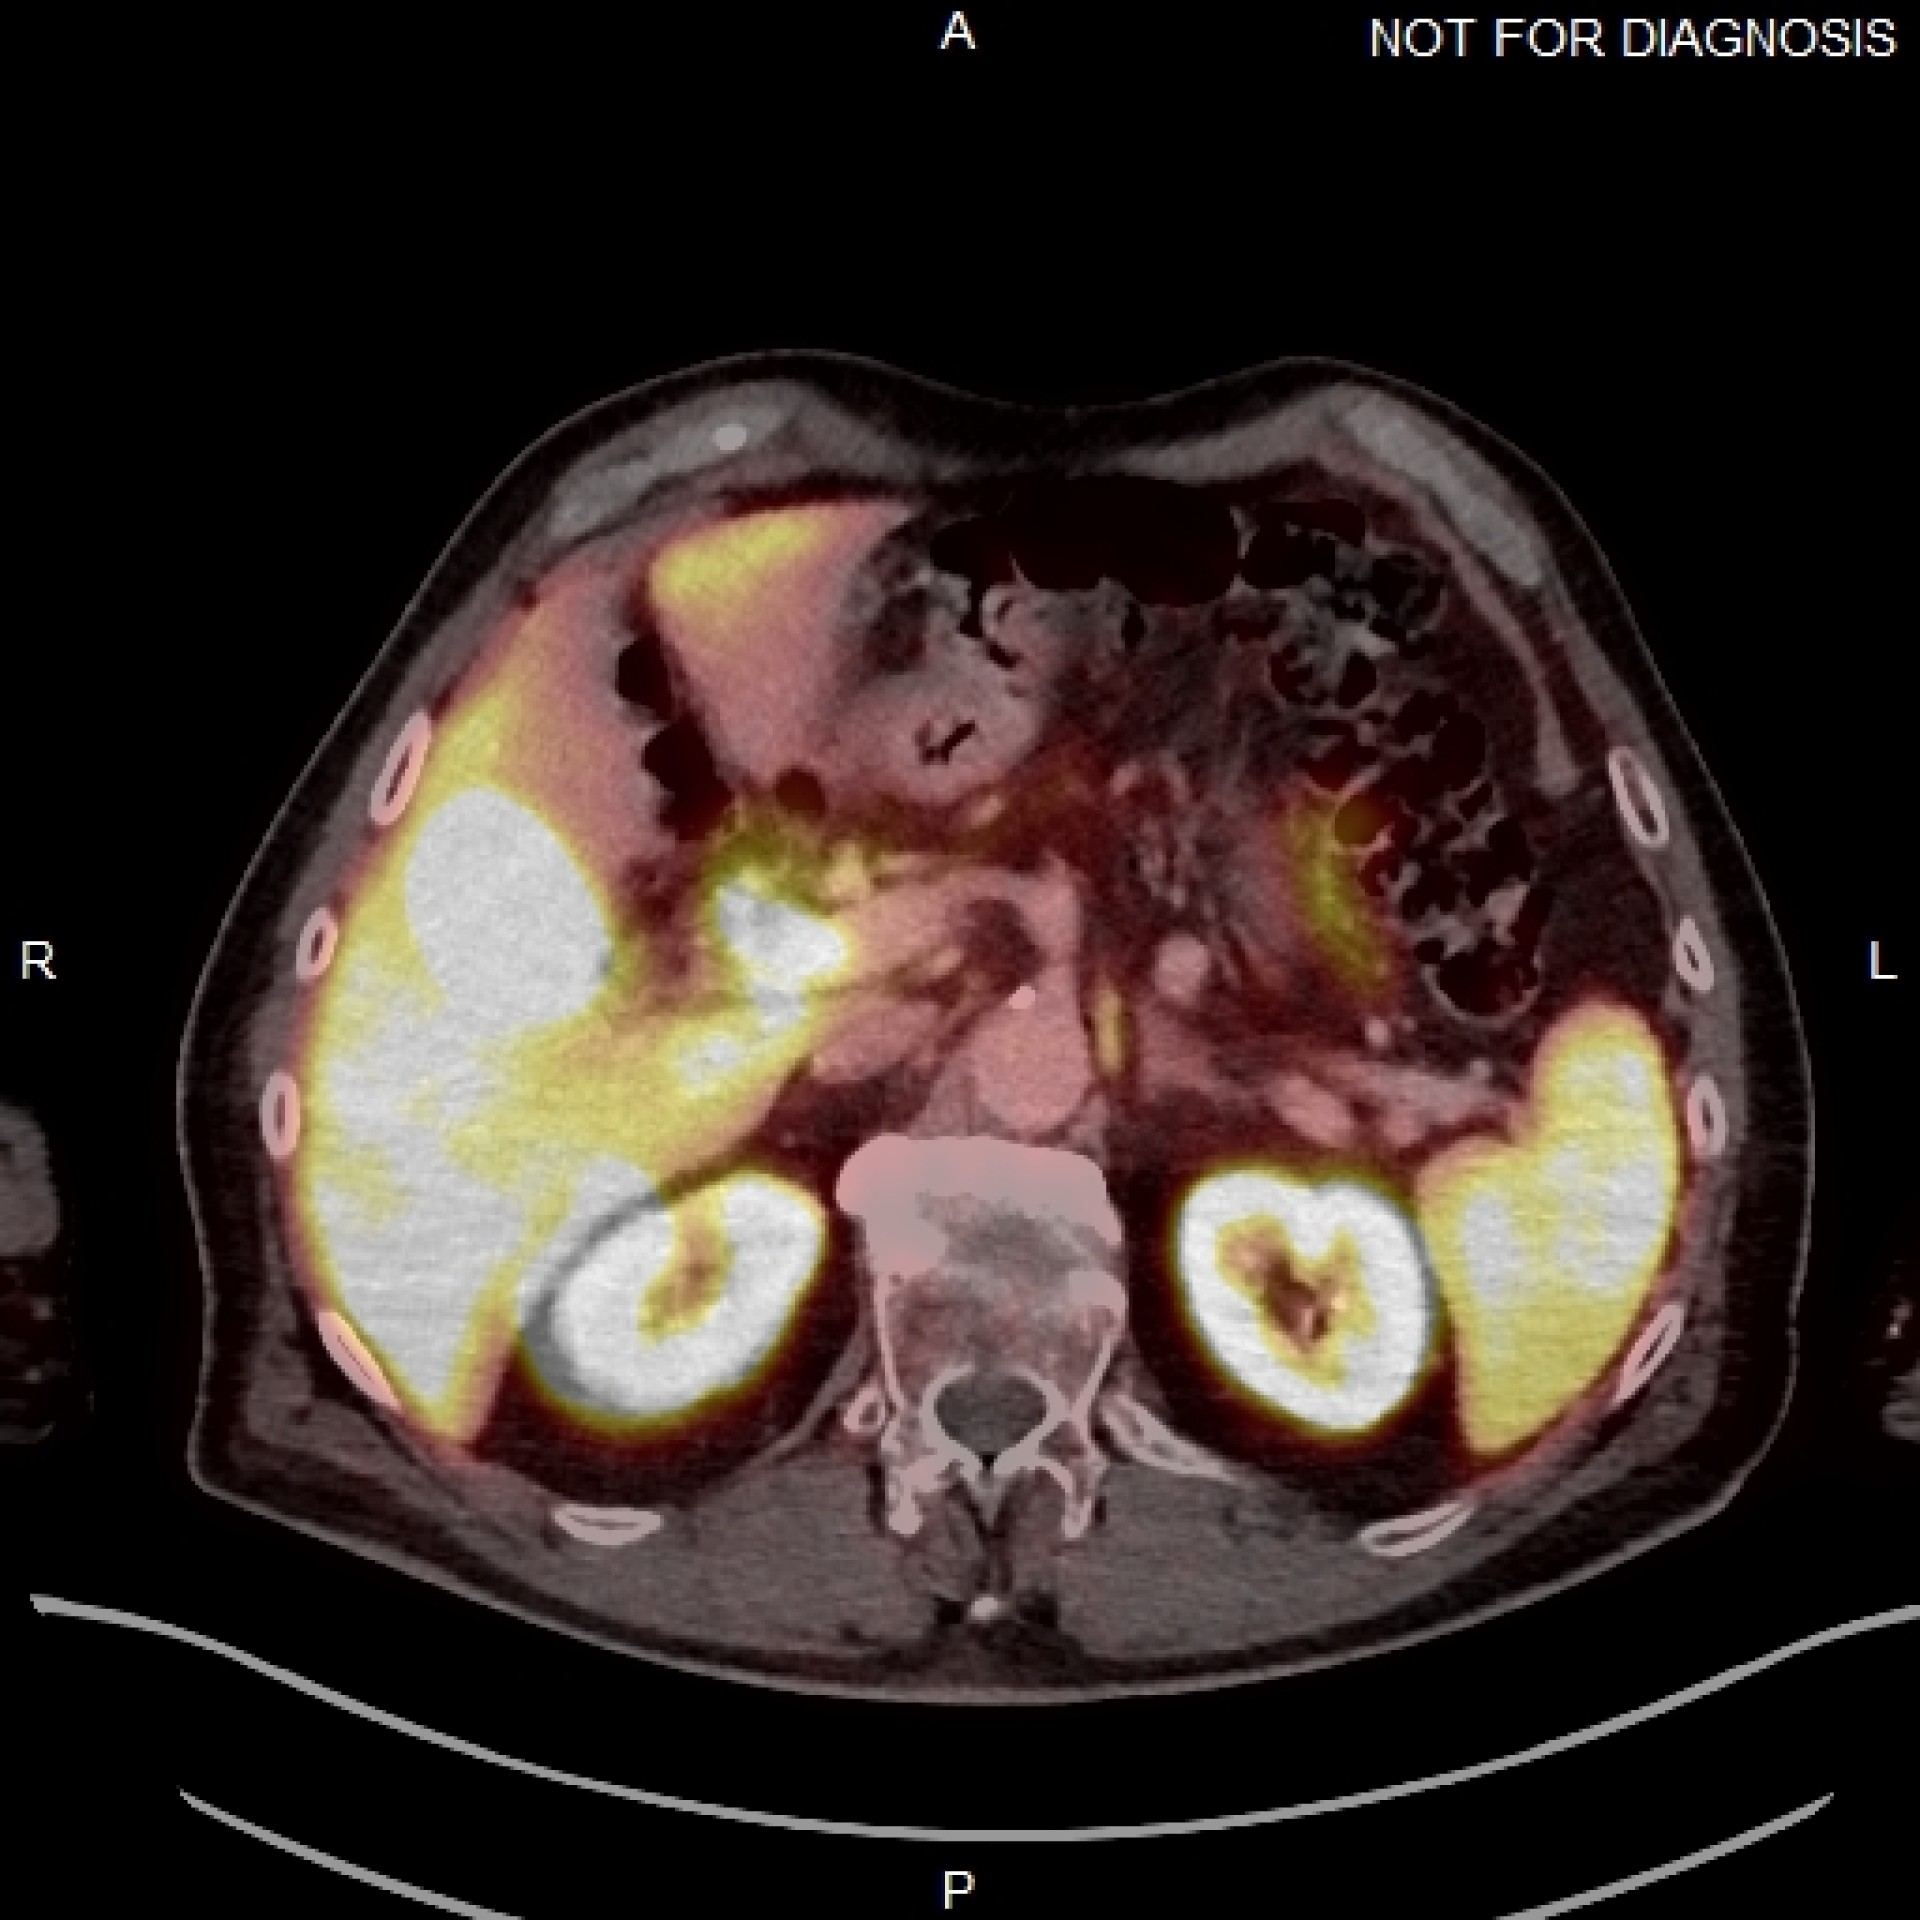

Histogram of uptake times for the Dublin group's patient cohort.All figures courtesy of Dr. Jane Burns, Prof. Martin O'Connell, et al, presented at EuroSafe 2025.

While one-third of the patients were within the EANM recommended uptake time range of 90 to 120 minutes, 65% of the cohort had an uptake time of less than 90 minutes, and two (1.5%) patients had an uptake time greater than 120 minutes.